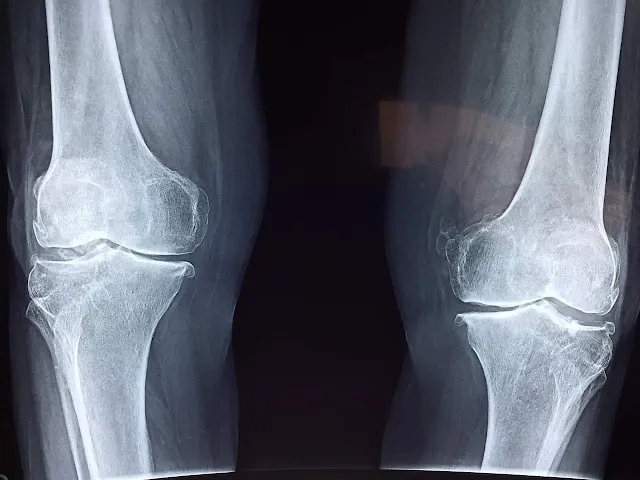

4. Imagerie par rayons X : pour vérifier la présence d'usure du cartilage ou de l'os.

L'arthrite : telles que l'arthrite rhumatoïde, l'arthrite dégénérative (épaississement), qui est la plus fréquente avec l'âge.